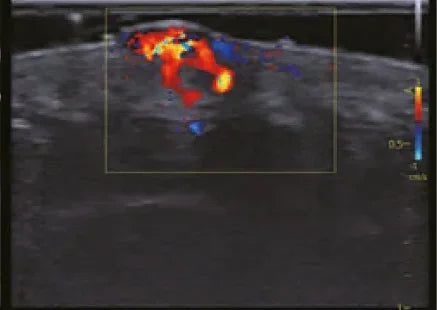

Ecografía Doppler: Qué es, Cómo Funciona y Qué Diagnósticos Permite

La ecografía Doppler es una herramienta clave para evaluar cómo circula la sangre a través de venas y arterias en...